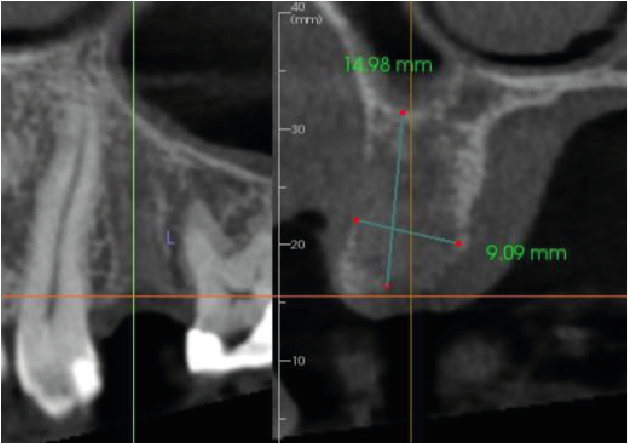

Image 2

The UL4 region has mild loss in vertical ridge height. The buccal cortical plate is thin or absent. There is Misch 4 bone density (Image 2).